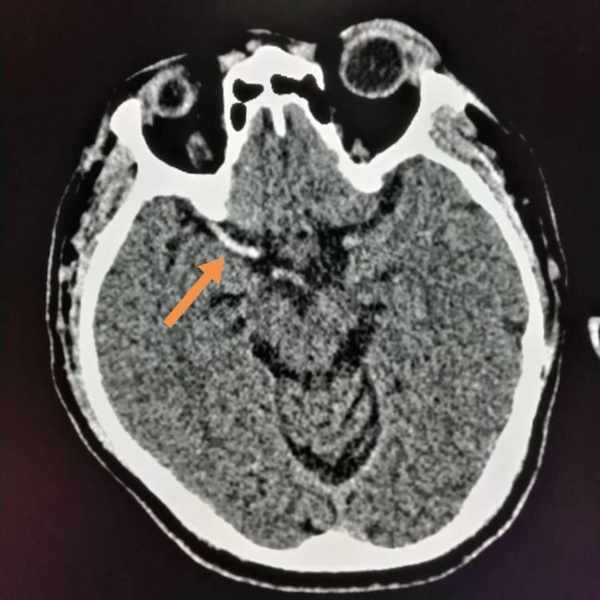

這位62歲的病人,淩晨被家人發現昏迷,急診CT發現右側大腦中動脈密度增高,呈緻密征,提示右側大腦中動脈急性腦梗死。

8小時後病情穩定下來,磁共振明確診斷,同時明確了梗死範圍: